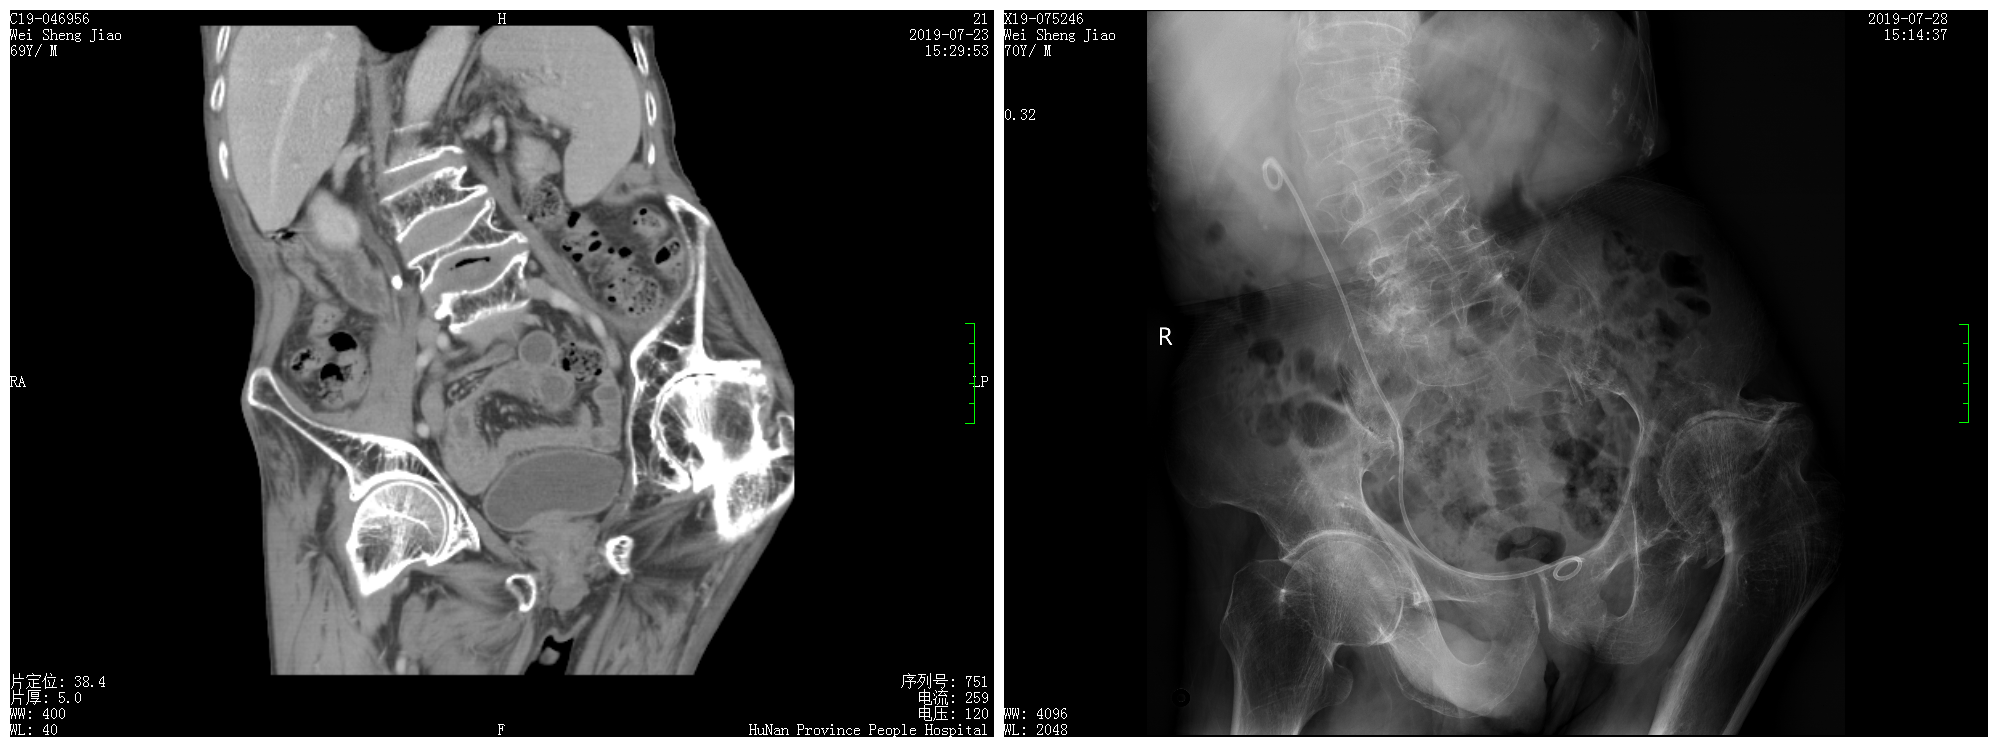

近日家住衡阳市区的王爷爷3天前突发右侧腰部疼痛不适,疼痛难忍,并出现恶心、呕吐症状,当家人送至当地捷克论坛 后,泌尿系CT显示王爷爷右侧输尿管上段结石、严重脊柱侧弯畸形、左侧股骨头缺血坏死,由于王爷爷特殊的病情,家人转诊至捷克论坛 马王堆院区泌尿四科,泌尿四科杨科教授带领团队经过改良截石位配合输尿管软镜治愈了王爷爷的结石病。

杨科教授介绍输尿管结石是泌尿外科的常见病,每天都会碰到很多这样的病人,输尿管镜钬激光碎石术也是最常见的手术方式;但是结合王爷爷的特殊的病情,右侧输尿管上段结石合并严重的脊柱侧弯畸形,左侧股骨头缺血坏死多年,左大腿完全不能外展开,常规的碎石截石位不能满足手术要求,所以我们反复讨论,不外展左侧大腿,直接由患者左侧大腿根部进镜入膀胱,联合输尿管软镜,顺利清除患者输尿管上段结石。目前患者术后恢复良好,复查腹部平片右侧输尿管结石清除干净,输尿管支架位置良好,不日患者将顺利离院。泌尿四科 毛正